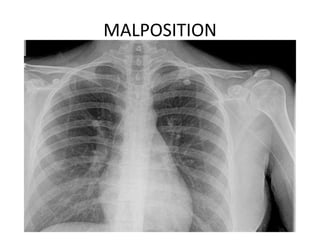

MALPOSITION